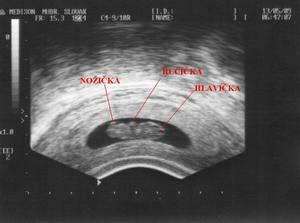

9. Červen: Velký ultrazvuk v Brně dopadl dobře. Ze zprávy "v děloze 1 plod, dle biometrie 12+0, morfologické anomalie nezastiženy, NB+, ASP+, linea nuchea 1,3 mm". Fotečku přikládáme dole, je na ní vidět hlavička a nosík, taky páteř. I když vyfotit se skoro nechtěl, hopsal nahoru a dolů jako na klouzačce. Od hlavičky k zadečku měříme přes 5,2 mm.🙂